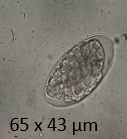

What does this image show?

Tapeworm eggs (Taenia)

Describe Taenia eggs

thick egg shell

radial striations

6-hooked (hexacanth) embryo inside